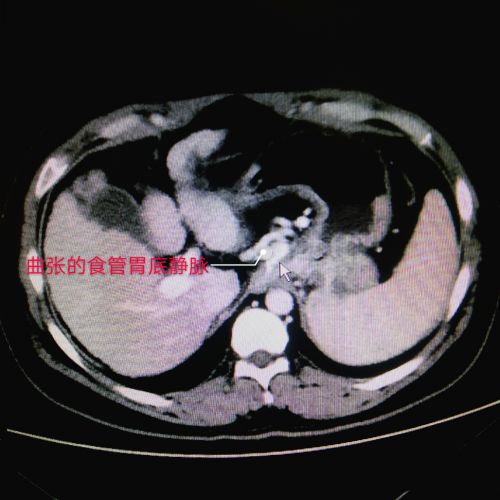

进一步检查后,王松被确诊为肝硬化引起的食管胃底静脉曲张,需尽早接受TIPS手术(经颈静脉肝内门体分流术)。手术需局部麻醉,医生担心王松不能配合,组织专家讨论病情,并制定了周密的手术方案和风险预案。

TIPS手术是从颈部穿刺进入肝内血管,置入支架,在肝脏内打造一条人工通道,从而降低血流压力,是治疗门静脉高压症合并静脉曲张破裂出血的重要介入技术,具有创伤小、适应症广、成功率高、疗效可靠等优点。应用这一技术可控制分流道的大小、适应不同个体需要,从而避免分流过度、降低肝性脑病的发生率。